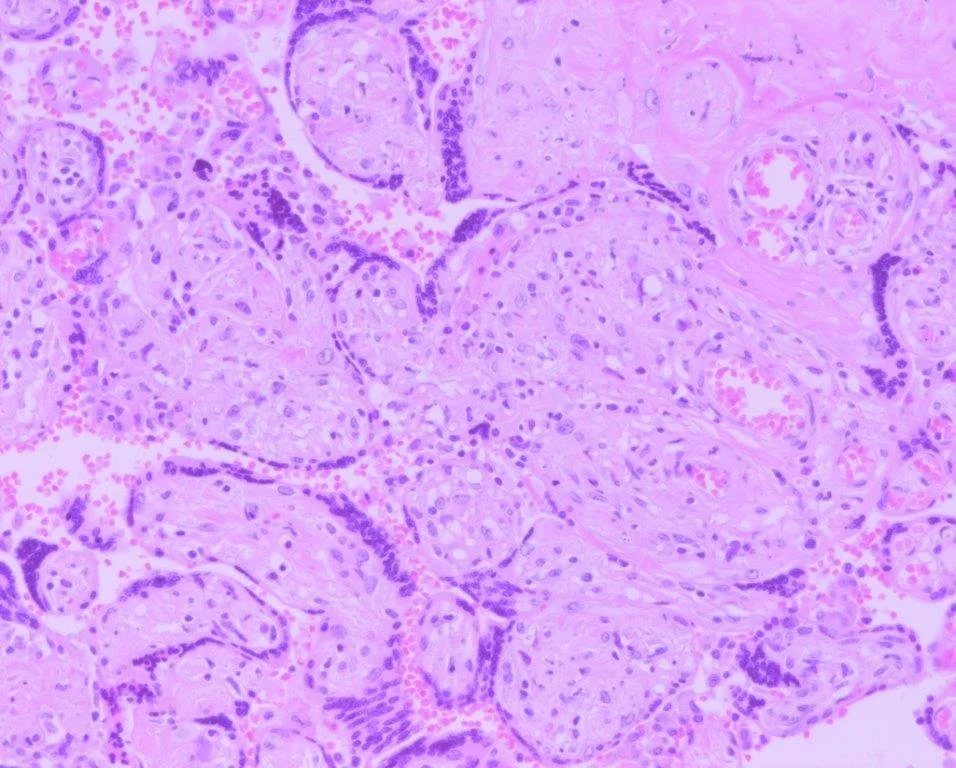

Examples of abnormal immune placentation

4. Chronic villitis of unknown/immune etiology (non‑infectious)

Other subtypes include massive perivillous fibrin deposition, placental infarcts, and chorioangiosis.